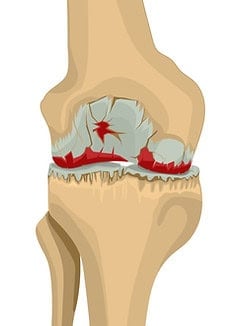

Arthrose oder Gelenkverschleiß ist eine sehr häufige degenerative Gelenkerkrankung, die jedes Gelenk betreffen kann. Am häufigsten sind die Gelenke betroffen, die das meiste Gewicht tragen, also Knie, Hüften und Wirbelsäule , oder jene, die im Alltag besonders stark beansprucht werden, etwa die Gelenke von Händen und Fingern. Arthrose kann auch eine Entzündung und Schmerzen verursachen; diese entzündliche Form wird als Osteoarthritis bezeichnet. Am häufigsten klagen Betroffene über Knieschmerzen. In den meisten Ländern werden die Begriffe Arthrose (Osteoarthrose) und Osteoarthritis klar unterschieden; im englischsprachigen Raum kommt es jedoch häufig zu Verwechslungen, selbst wenn keine Entzündung vorliegt.

Arthrose entsteht, wenn der Gelenkknorpel dünner wird und die Oberfläche aufraut. Dies geschieht durch dauerhafte Belastung und ist im Alter häufig. Begünstigende Faktoren sind unter anderem Geschlecht, Übergewicht und genetische Veranlagung. In einem gesunden Gelenk ist die Knochenoberfläche von glattem, gleitfähigem Knorpel bedeckt, der eine nahezu reibungslose Bewegung ermöglicht. Bei Arthrose nutzt dieser Knorpel ab, die Reibungnimmt zu und es können mit der Zeit Beschwerden entstehen. Der Körper startet dann Reparaturprozesse im Gelenk, die dessen Struktur verändern und häufig wieder eine schmerzfreie Funktion ermöglichen. Mit zunehmendem Alter haben die meisten Menschen in irgendeinem Gelenk eine Arthrose, oft ohne es zu bemerken. Tatsächlich findet man Arthrose bei mehr als 10 % der unter 40-Jährigen, bei über 40 % der über 40-Jährigen und bei 60 % der über 65-Jährigen ; weniger als die Hälfte der Betroffenen hat dabei Knieschmerzen.

Allerdings verlaufen diese Reparaturprozesse nicht immer reibungslos, und Veränderungen im Gelenk können manchmal zu Entzündungen, Knieschmerzen, Schwellungen und Bewegungsstörungen. Dies kann durch die folgenden Prozesse geschehen:

- Bildung von knöchernen Fortsätzen (Osteophyten): An den Gelenkrändern können sich knöcherne Ausziehungen bilden, die die Beweglichkeit einschränken oder am umliegenden Gewebe reiben. An den Fingerknöcheln zeigt sich dies oft als sichtbare, knotige Verdickungen.

- Entzündung der inneren Gelenkkapsel : Sie verursacht Knieschmerzen und eine erhöhte Produktion von Gelenkflüssigkeit, was zu Schwellungen, Schmerzen und eingeschränkter Beweglichkeit führt.

- Bänder und Muskeln: Die Muskulatur und Bänder rund um das Gelenk können überdehnt werden, wodurch das Gelenk im Laufe der Zeit an Stabilität verliert.